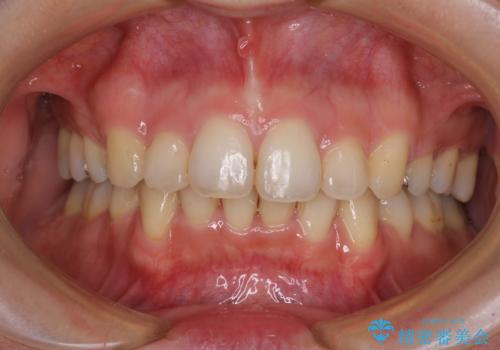

- 前歯のデコボコを気にして来院された患者様です。

上顎右側犬歯が八重歯になっており、それによって奥歯が前方に移動しているため、右側の咬み合わせの改善が必要と判断されました。

マウスピース矯正では改善に時間がかかる、あるいは改善しきれない可能性があることを伝えたところ、短期間で確実に治療ができるワイヤー矯正を選択されました。

より治療を速やかに行うため、上顎右側にアンカースクリューを使用し、目標としていた1年半ほどで治療を終えることができました。